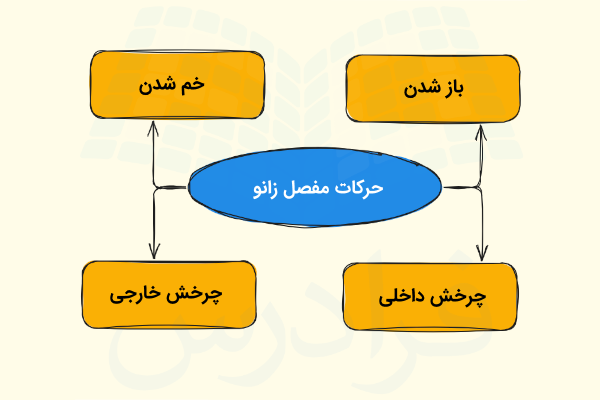

حرکات زانو

زانو یکی از مفصلهای لولایی بدن است که به طور عمده حرکات آن به صورت خم و باز شدن زانو در «سطح ساژیتال» (Sagittal Plane) قابل مشاهده میباشد، اما در دو حالت زیر امکان چرخش داخلی محدود این مفصل وجود دارد.

- زانوی خم شده

- در مرحله پایانی باز شدن زانو

علاوه بر زمان خمیدگی زانو، امکان چرخش جانبی یا خارجی زانو در حین باز کردن آن نیز وجود دارد. در نتیجه باید گفت که مفصل زانو دارای چهار نوع حرکت است که به کمک ماهیچههای متفاوتی انجام میشود، در ادامه ماهیچههای مسئول هر حرکت را معرفی میکنیم.

- «باز شدن» (Extension): توسط «ماهیچه چهارسر ران» (Quadriceps Femoris) انجام میشود.

- «خم شدن» (Flexion): این حرکت توسط عضلات همسترینگ، گراسیلیس، سارتوریوس و پوپلیتئوس انجام میشود.

- «چرخش خارجی» (Lateral Rotation): ماهیچه دو سر رانی مسئول انجام این حرکت است.

- «چرخش داخلی» (Medial Rotation): پنج ماهیچه نیموتری، نیمغشایی، گراسیلیس، سارتوریوس و پوپلیتئوس مسئول این حرکت هستند.

با این توضیحاتی که ارائه شد متوجه میشویم که برخلاف مفصل آرنج، مفصل زانو را نمیتوان یک مفصل لولایی واقعی به حساب آورد؛ زیرا این مفصل دارای یک جزء چرخشی است که باعث میشود زانو در حین باز و بسته شدن حرکت خارجی نیز داشته باشد. در نتیجه این امر، زانو «مفصل لولایی تغییر یافته» (Modified Hinge Joint) به حساب میآید. میزان خم شدن زانو به دو نکته زیر بستگی دارد.